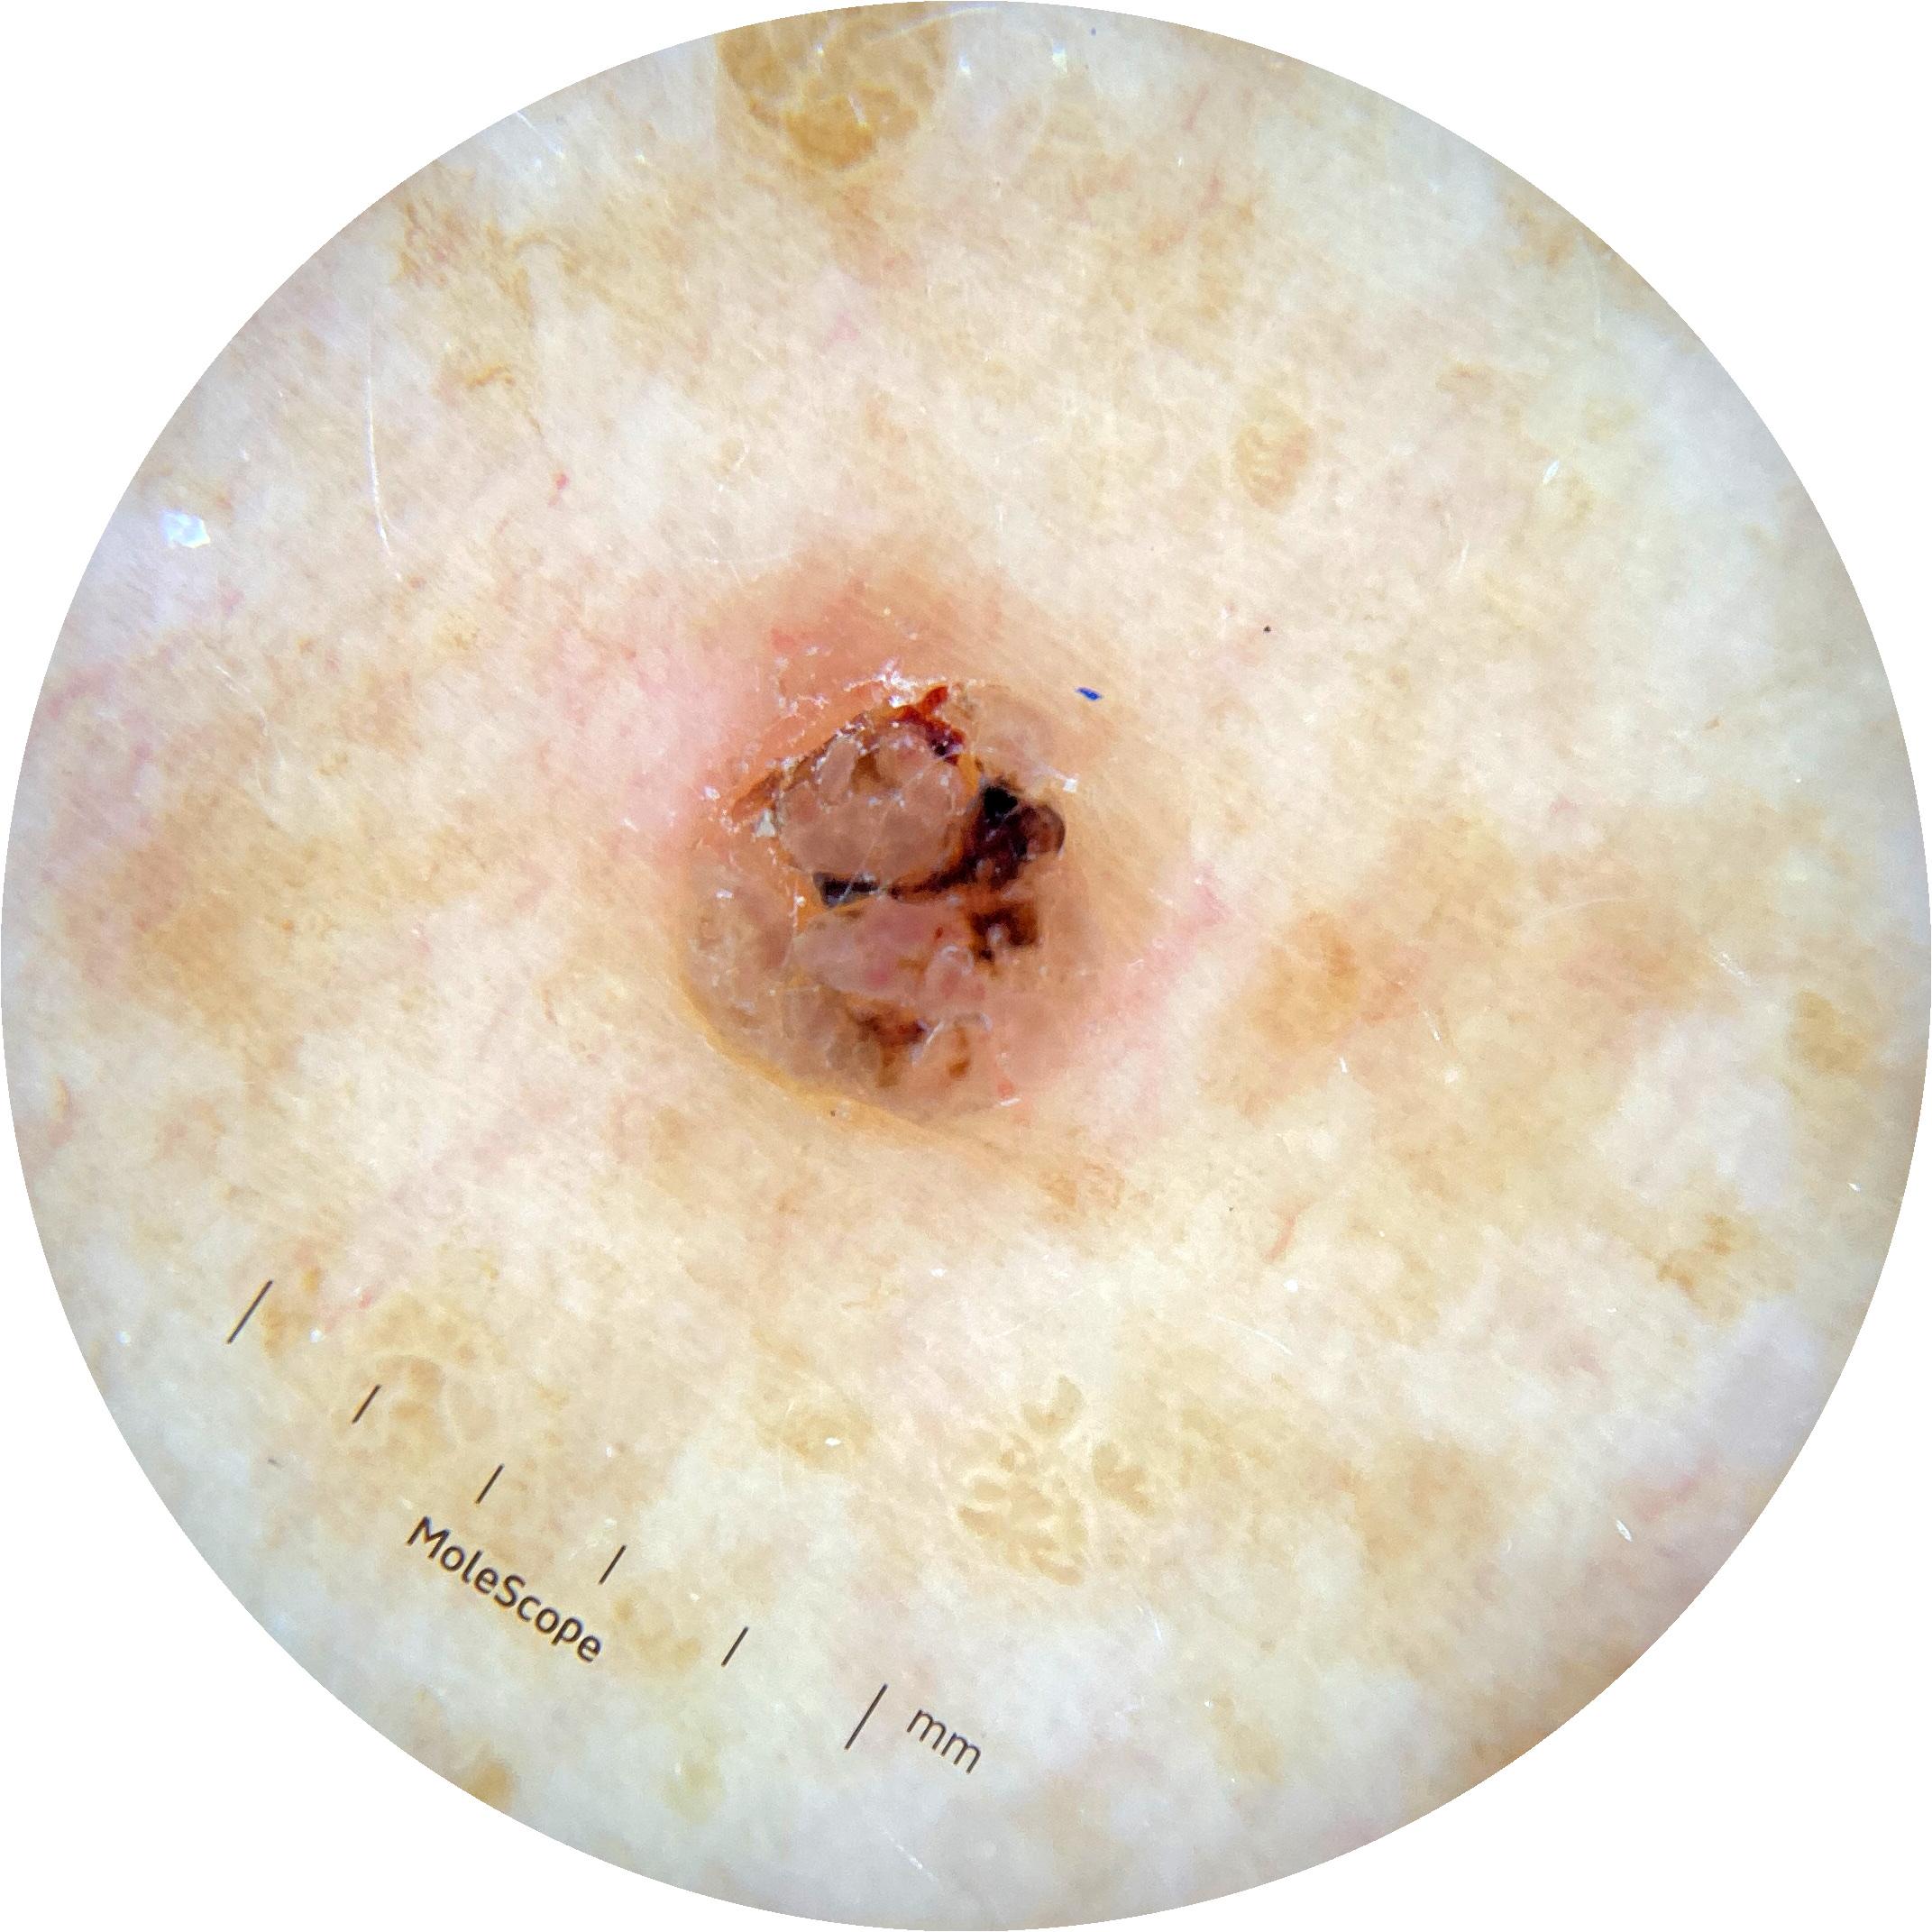

ISIC_8528385

Clinical

acquisition_day 27

age_approx 60

anatom_site_1 Upper extremity

diagnosis_1 Benign

diagnosis_confirm_type single image expert consensus

fitzpatrick_skin_type I

image_type dermoscopic

sex female